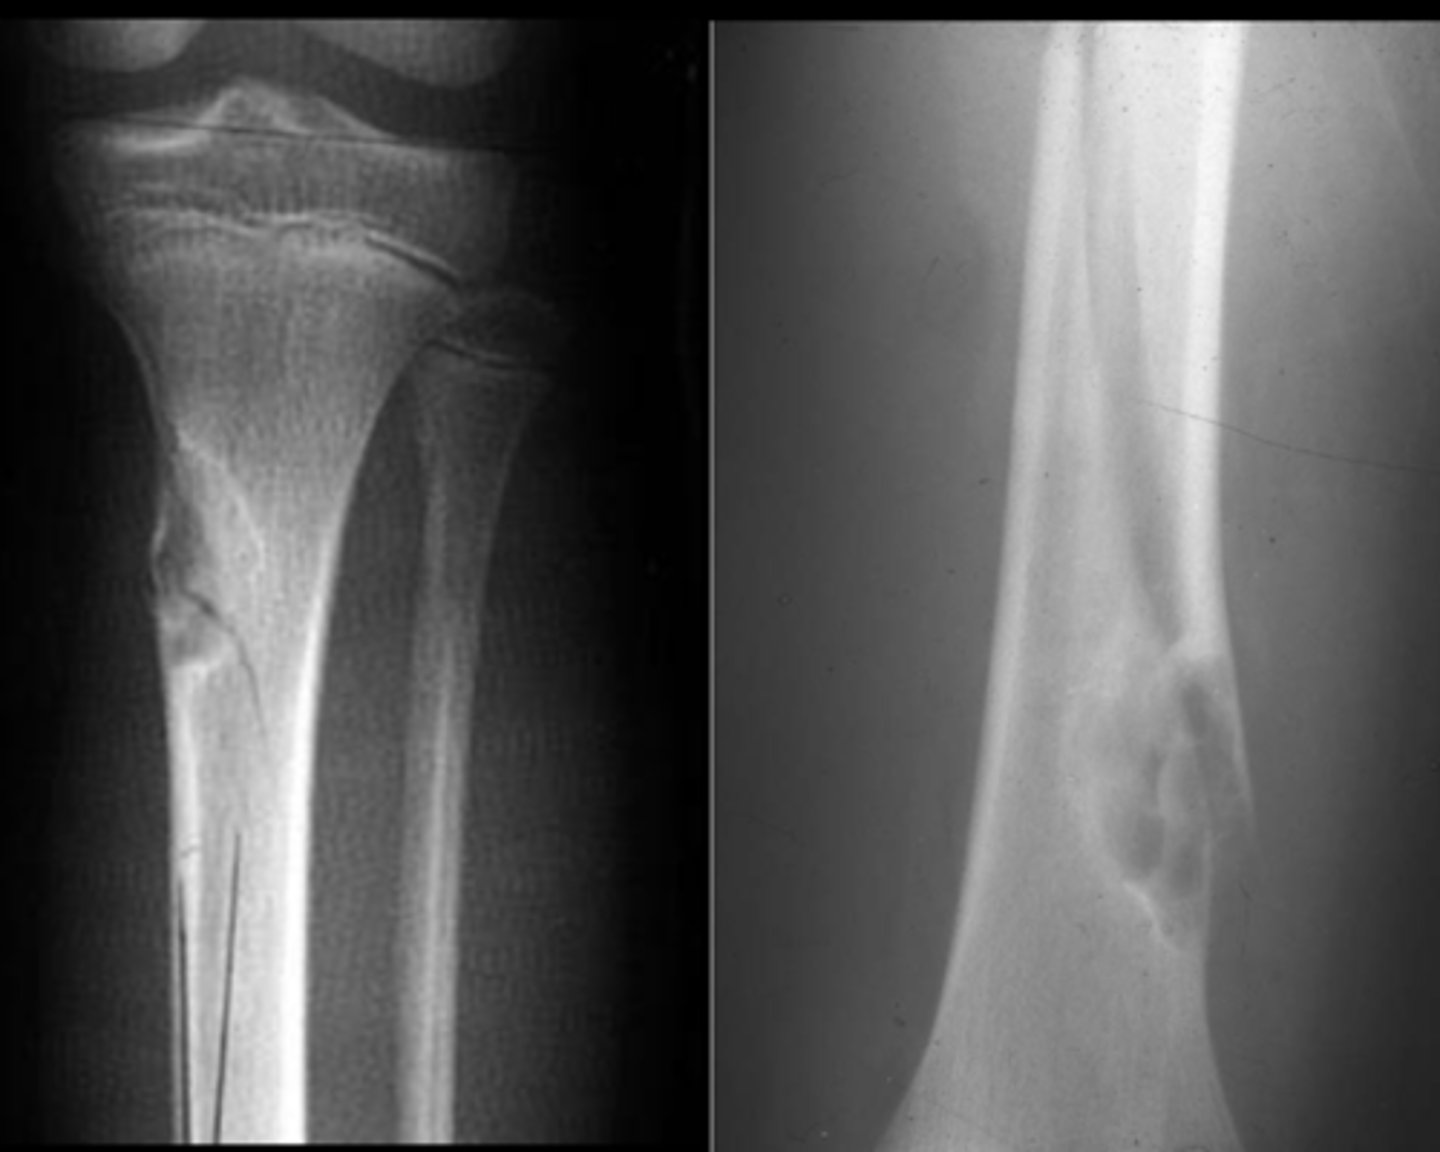

Geographic bone blister

ID radiographic feature of non-ossifying fibroma indicated by top arrow

<p>ID radiographic feature of non-ossifying fibroma indicated by top arrow</p>

59

New cards

Septations

ID radiographic feature of non-ossifying fibroma indicated by bottom arrow

<p>ID radiographic feature of non-ossifying fibroma indicated by bottom arrow</p>

60

Pathologic fracture

Non-ossifying fibroma with _____

<p>Non-ossifying fibroma with _____</p>